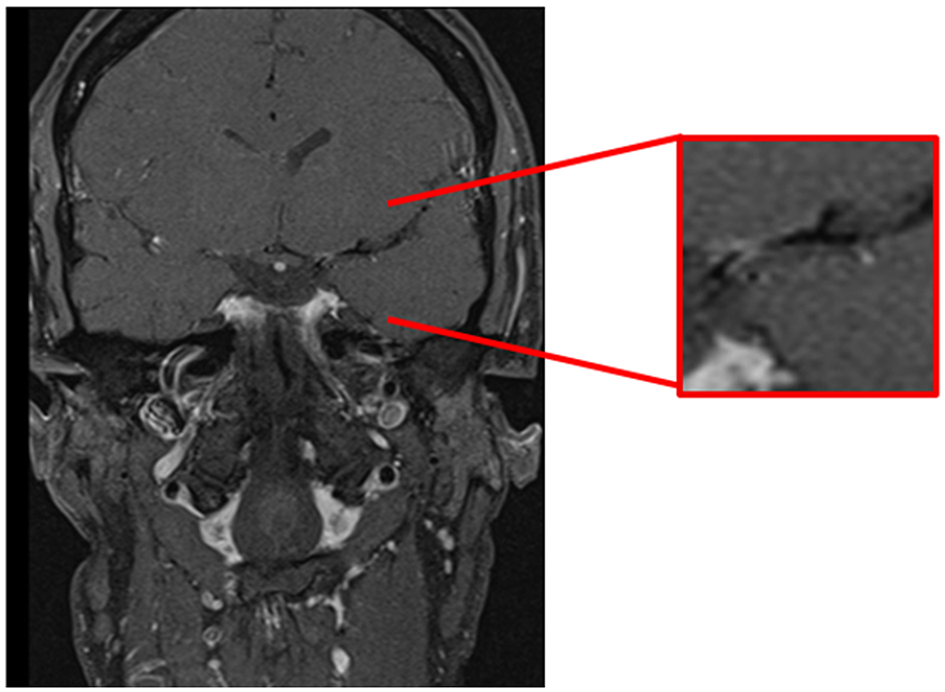

Commonly used imaging modalities fail to distinguish between inflammatory and non-inflammatory vasculopathies. Preliminary studies demonstrated the possibility of outlining the vessel wall by contrast enhancement (40–42). In enhanced MR imaging of the vessel walls (“dark blood imaging”) the signal of the blood is suppressed and discrimination of the vessel wall from the lumen is increased (Figure 2). This HR-MRI can be performed as T1-weighted, T2-weighted or proton density-weighted sequences (43). This technique has already been used to distinguish PACNS from other vasculopathies (40, 42). In more detail, in PACNS a predominantly smooth, concentric, and long-segment wall thickening with strong enhancement and a perivascular edema were observed (44). Arteriosclerotic plaques exhibit a more eccentric, irregular, and short-segment wall thickening without perivascular edema and only mild enhancement depending on composition and activity of the plaque (25, 42). However, the distinction might still be difficult and this MRI sequence might rather help to differentiate PACNS from vasculopathies of young adults such as RCVS (41, 44). Notably, HR-MRI is merely capable of detecting the MVV with its current capacity of vessel resolution. However, this imaging technique is quickly developing and might soon lead to an improved discrimination between the MVV of PACNS and other intracranial vasculopathies (45). Of note, with higher resolutions it will be able to detect changes even in small vessels. Given that treatment can also affect the imaging findings, e.g., less enhancement under immunosuppressive or antiviral therapy (43, 46), it might also have the potential to monitor disease activity, which would make it extremely valuable for clinical trials (43, 47).

Figure 2

Cranial MRI, coronal T1-weighted-(dark-blood) sequence demonstrating contrast enhancement of the vessel wall in the first segment of the left middle cerebral artery.